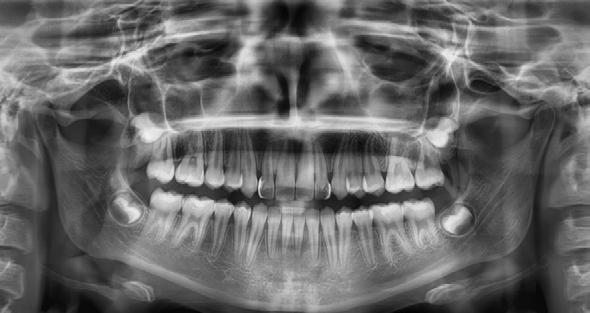

Radiografía panorámica. Se ven 34 dientes (Figura 3), con el canino 13 retenido y los órganos denatrios 75 y 85 están próximos a ser exfoliados. Los segundos molares aún están terminando su formación y aparece el germen dentario de los terceros molares.

Figura 2. Intraorales frente lateral derecha e izquierda. Figura 3. Radiografía panorámica inicial.

Radiografía panorámica final el canino 13 es incorporado al arco (Figura 5) y los terceros molares en etapa de formación.

Figura 5. Radiografía Panorámica. Figura 6. Comparación inicio-final en oclusión.